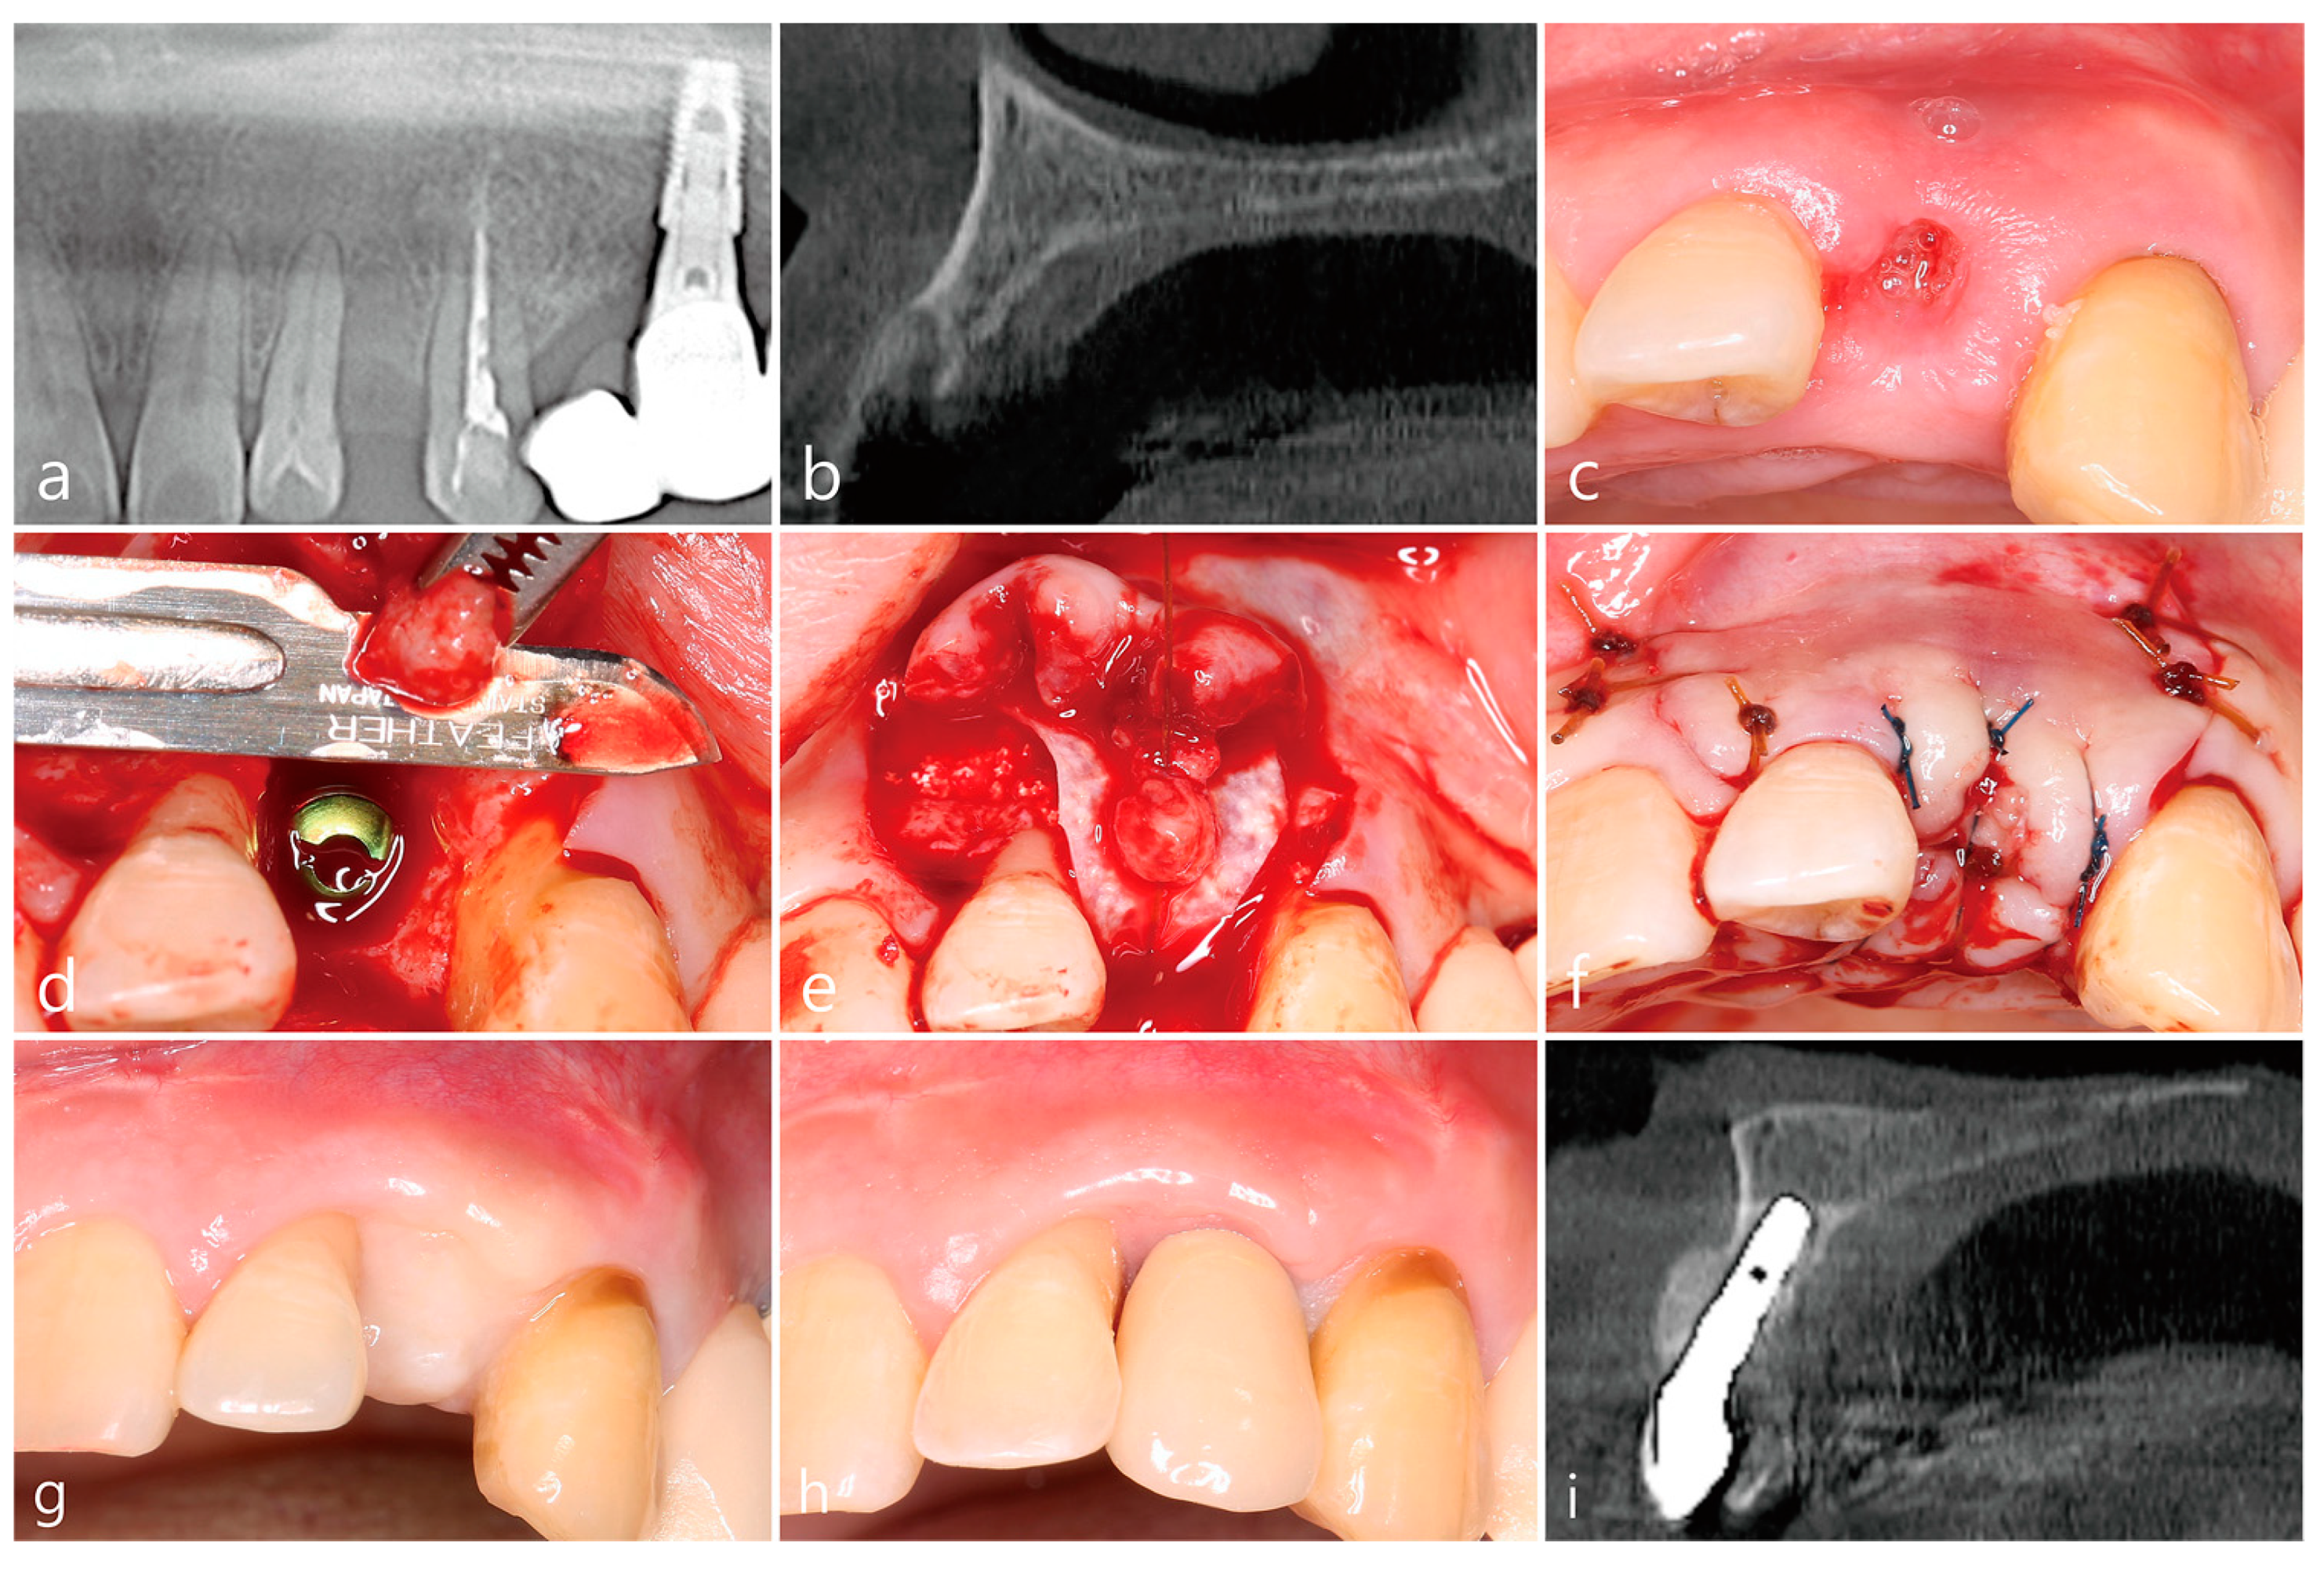

4. Case 2

- A tooth or implant with severe bone loss was removed using extraction forceps under local anesthesia with 2% lidocaine containing 1:100,000 epinephrine;

- A midcrestal incision and two buccal vertical incisions were made. Before raising the flap, special care was taken to ensure a clean dissection of the IGT from the underlying flap without any damage and the IGT is still well-attached to the flap. The IGT was then further separated from the bony housing by using a curette with various curvatures and a periosteal elevator.

- The IGT attached to the buccal flap was dissected to an appropriate thickness using a #15 blade so that the base of the IGT was still attached to the existing flap, and the flap was eventually extended. Periosteal releasing incisions were not performed at the flap base.

- The extraction socket was thoroughly debrided using a Molt curette and a titanium brush.

- A surgical guided stent was used so that the implant (Implantium, Dentium, Suwon, Korea) was placed 2.0 mm subcrestal to the level of the adjacent bone in the extraction socket.

- A synthetic osteoconductive bone graft substitute composed of hydroxyapatite (HA) and beta-Tricalcium phosphate (β-TCP) (Osteon III, Genoss, Suwon, Korea) and a resorbable collagen membrane (Genoss, Suwon, Korea) were placed to cover the implant and the peri-implant osseous defect.

- After covering the bone graft with the collagen membrane, the extended IGT was sutured with the palatal flap with 4-0 Catgut. Next, the buccal flap was closed using 4-0 nylon or black silk.

- Uncovering procedures were performed 4–6 months after initial surgery. Under local anesthesia, the buccal flap was reflected, the regenerated tissue above the implant cover screw was removed, and the healing abutment was connected to the implant. The buccal flap was closed using 4-0 Catgut or black silk. Antibiotics and anti-inflammatory drugs were prescribed for 5 days. The prosthesis was installed 2 months after uncovering.